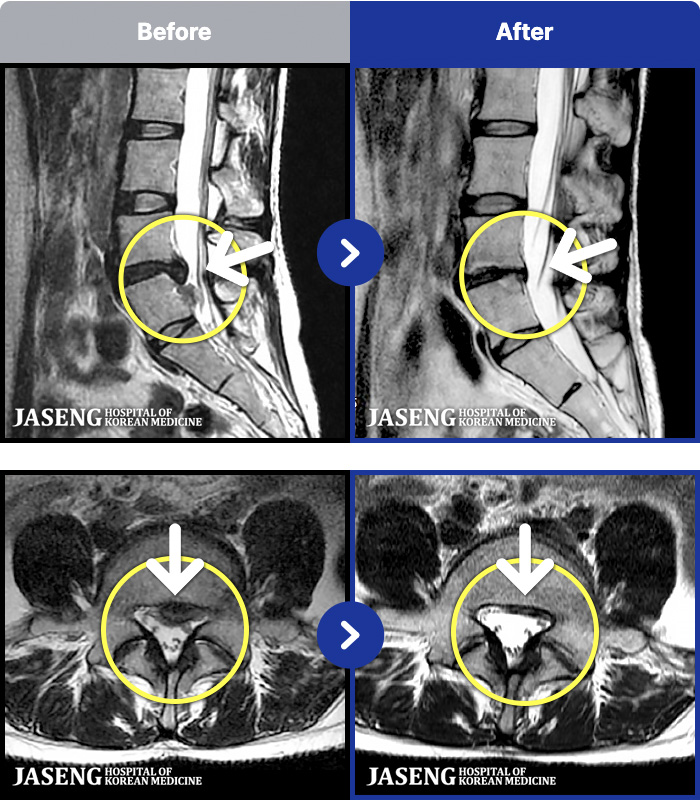

- MRI ġ

MRI ġ

191 MRI ũ ʸ Ȯϼ.

[_㸮ũ] ٸ 㸮 ȹٷ , Բ 㸮 ־ ߴ.

[_㸮ũ] ؽ ð ɾ ְų ִ ڼ ¿.